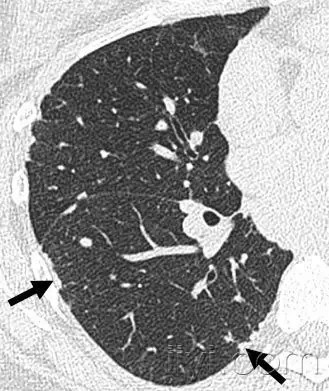

小叶中心性

解剖:小叶中心性用于描述次级肺小叶的支气管血管束中心区域。病理学上也用这一术语描述终末小支气管远端,位于呼吸性细支气管和肺泡管中心的病变。 医学百科网 | YxBaike.Com

CT:正常次级肺小叶中心的点状或者线状的密度增高影,胸膜下25px范围内最明显,代表小叶内的动脉,直径约1mm。小叶中心性异常包括(1)结节(2)树芽征,提示小气道病变(3)由于临近间质的增厚或者浸润导致小叶中心结果更加清晰(4)小叶中心性肺气肿导致的异常低密度。 医学百科网 | YxBaike.Com

附图为小叶中心性肺气肿 医学百科网 | YxBaike.Com